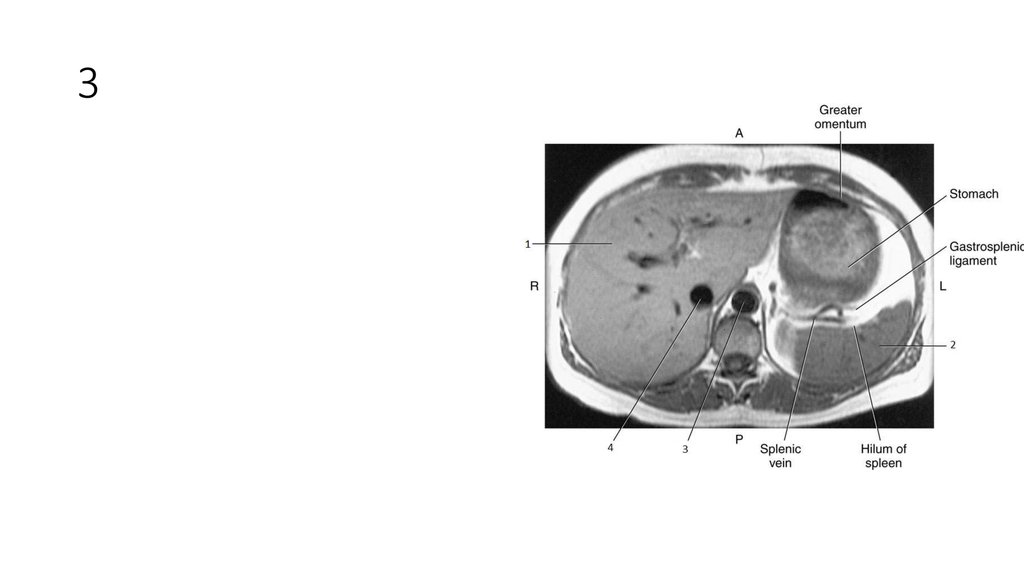

6. 3

7. 3

• Aorta

14. 3

15. 3

• Liver

21. 3

• Spleen